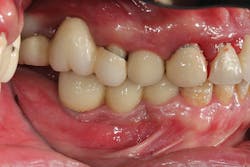

Implant manufacturing involves a high degree of precision. Implant fixture dimension, bone drill protocols, taps, and insertion devices should intimately correspond. Prosthetic components, abutment connections, and screws are also closely mated in design and production, so there is minimal tolerance between machined components. Interestingly, I hear much conversation regarding the poor fit of lower-tiered implant components, which can result in implant failure or screw loosening. Implant systems consist of CAD/CAM parts, with components that are fabricated with a high degree of homogeneity. Vertical and anti-rotational discrepancies exist and vary between companies and the types of connection used,12 but studies indicate that the fit of mismatched components improves with the application of mechanical torque to a clinically acceptable level.13 Clinicians also need to understand that there is more to screw loosening than the system-such as passive fit of the casting, proper torque values and preload,14 adequate interproximal contact, and the most often overlooked and misunderstood aspect of dentistry . . . occlusion (figures 7-9).

Figures 7-9: Implant site No. 19 has been restored for one year without any incident of screw loosening. Bone levels are excellent (figure 7), but a small gap is evident between the abutment and fixture platform upon radiographic evaluation (figure 8), due to the usage of implants from two "compatible" manufacturers. The tissue levels are excellent, despite a "mismatch" in components. Notice the gingival recession and the lack of attached tissue15,16 on distal implant site No. 18 (figure 9). However, with critical examination of implant No. 18, it is possible that the transmucosal element is too long and the overlying gingival tissues too thin, making this particular fixture inappropriate for this site. (Perhaps a bone-level fixture would have been a better choice.)